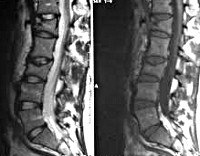

Всем больным с переломами позвонков назначают рентгенографию поясничного отдела позвоночника в двух проекциях. Наиболее информативен боковой снимок, на котором выявляется снижение высоты передних отделов позвонка. Для оценки состояния нервных структур пациентов направляют на консультацию к нейрохирургу или неврологу. Используют МРТ позвоночника, позволяющее выявить наличие или отсутствие и степень повреждения нервных структур. При необходимости проводят КТ позвоночника, электрофизиологические исследования, миелографию и ликвородинамические пробы.

Диагноз устанавливается на основании характерного анамнеза, симптомов и результатов рентгенографии позвоночника. Снимки выполняются в двух проекциях, наиболее информативна боковая проекция. На рентгенограмме выявляется снижение высоты и клиновидная деформация одного или нескольких позвонков. При необходимости для оценки состояния спинного мозга и его оболочек, а также связок и хрящей позвоночника, назначают МРТ или КТ позвоночника. При наличии неврологических нарушений больного направляют на консультацию к неврологу или нейрохирургу. Для выявления и более точной оценки степени повреждения спинного мозга применяют миелографию.

При подозрении на патологический перелом, обусловленный опухолью или метастазом, необходимо проведение МРТ или радионуклидного исследования. При подозрении на остеопороз назначают денситометрию и электрофорез белков сыворотки крови. Молодым пациенткам с остеопорозом показана консультация эндокринолога для исключения гиперпаратиреоза.